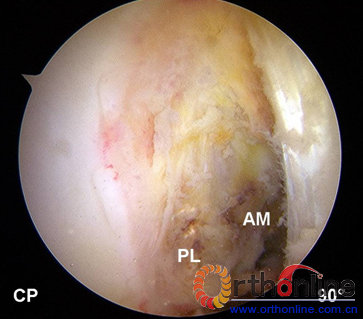

传统上ACL的关节镜入路仅是前内和前外入路。解剖重建时,由于对视野要求更高,因此需要构建新的手术入路。ACL解剖重建常规使用三个入路,前外(LP)、中间(CP)和前内辅助入路(AMP)。前外入路:置于关节间隙以上,紧贴髌腱外侧缘,用以观察胫骨止点,此入路一般置于偏上的位置有利于避开髌下脂肪垫组织。[22]中间入路:置于内侧关节间隙略偏上位置,紧贴髌腱内缘,或者经过部分髌腱组织,可用于全面探查髁间窝外侧壁和AM、PL的股骨止点。前内侧辅助入路:置于内侧关节间隙以上,距离髌腱内侧缘大约2cm,该入路为器械入路,可用于股骨止点的定位和钻取骨道。

右膝关节ACL重建入路位置,前外入路(LP),中间入路(CP)和前内辅助入路(AMP)。

右膝关节屈膝90度,由中间入路进镜,可直接观察到ACL的股骨止点位置,髁间窝外侧壁。